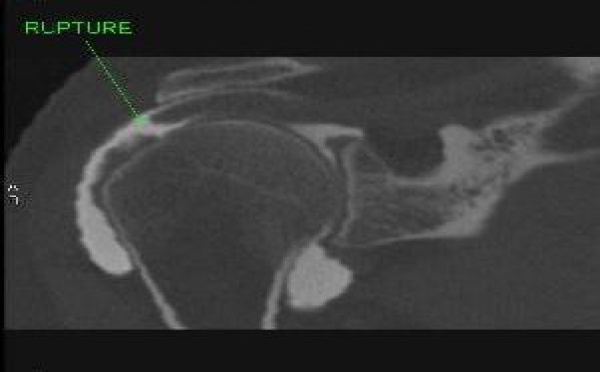

Les limites de l’arthroscanner de l’épaule

Ne pas conclure trop vite à l’absence de rupture…